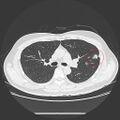

5. 2023/10/20 조영제 CT 촬영

2. 대표사진 - 사진 속 빨강 원이 문제의 결절

3. 사진을 동영상으로 변환. 노랑 원이 문제의 결절